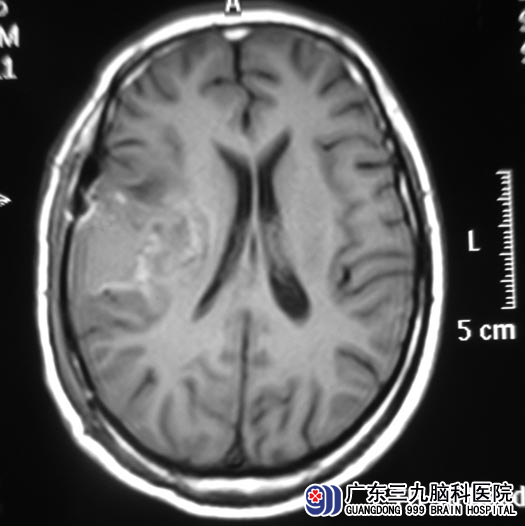

5月25日,由综合神经外科 鲁明主任主刀行右额叶肿瘤切除术,术中见局部脑组织色泽改变明显,导航定位肿瘤位置,皮层电生理监测确定功能区位置,术中使用唤醒麻醉让李先生言语及肢体功能配合,肿瘤在镜下全切,手术过程顺利。术后左侧肢体活动较前好转,语言及肢体活动功能未有受损。已康复出院。术后病理结果为:少突胶质细胞瘤。后期李先生仍需要做进一步的放化疗。

▲手术后